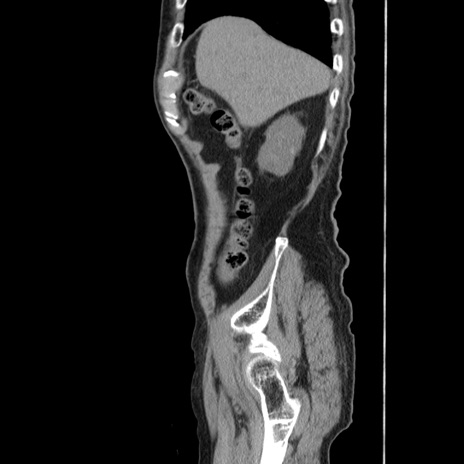

症例24(矢状断像)

【症例】80歳代男性

【主訴】左側腹部痛、嘔吐

【現病歴】本日早朝より左腹部に痛みあり。昼頃嘔吐認めたため、救急要請。

【既往歴】直腸癌(Mile手術)、胆摘

【身体所見】意識清明、BT 35.9℃、BP 221/93mmHg、SpO2 97%(RA) 、腹部:左ストーマ周囲に限局性の腹部膨隆あり。 膨隆部自発痛・圧痛あり・軟。

【データ】WBC 7700、CRP 0.09